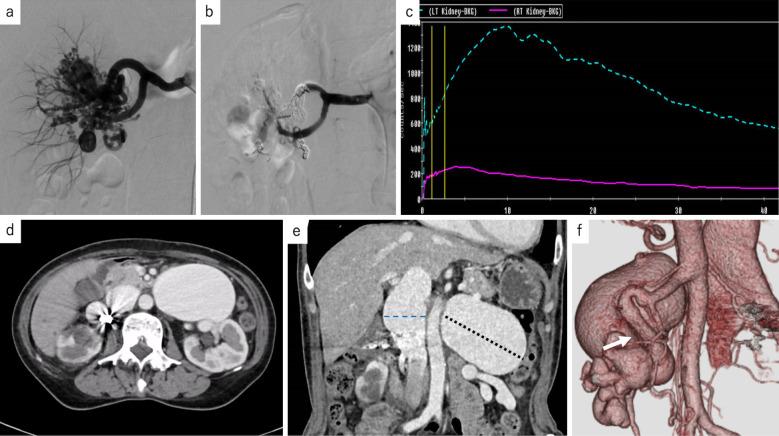

Although transcatheter arterial embolization is the first choice treatment for renal arteriovenous malformation. Renal arteriovenous malformation with dilated venous sac can cause venous pulmonary thromboembolism after transcatheter arterial embolization. A woman in her 60s was diagnosed with a left renal arteriovenous malformation and an 8 cm venous sac with renal dysfunction after right renal arteriovenous malformation treatment. We performed a hybrid treatment of transcatheter arterial embolization and sequential vein ligation to reduce the risk of lethal thrombotic complications. After treatment, the left renal arteriovenous malformation disappeared without fatal complications, and the venous sac shrunk with the preservation of renal function as it was before the hybrid treatment. When performing embolization of renal arteriovenous malformation with a huge venous sac, hybrid treatment of arterial embolization and surgical vein ligation may be safe and useful for preventing fatal post-operative thrombotic complications.

尽管经导管动脉栓塞术是肾动静脉畸形的首选治疗方法。伴有扩张静脉囊的肾动静脉畸形在经导管动脉栓塞术后可导致静脉肺血栓栓塞。一名60多岁的女性在右侧肾动静脉畸形治疗后被诊断为左肾动静脉畸形和一个8厘米的静脉囊,并伴有肾功能不全。我们进行了经导管动脉栓塞术和序贯静脉结扎的联合治疗,以降低致命血栓并发症的风险。治疗后,左肾动静脉畸形消失,无致命并发症,静脉囊缩小,肾功能保持在联合治疗前的水平。当对伴有巨大静脉囊的肾动静脉畸形进行栓塞时,动脉栓塞和手术静脉结扎的联合治疗对于预防致命的术后血栓并发症可能是安全有效的。